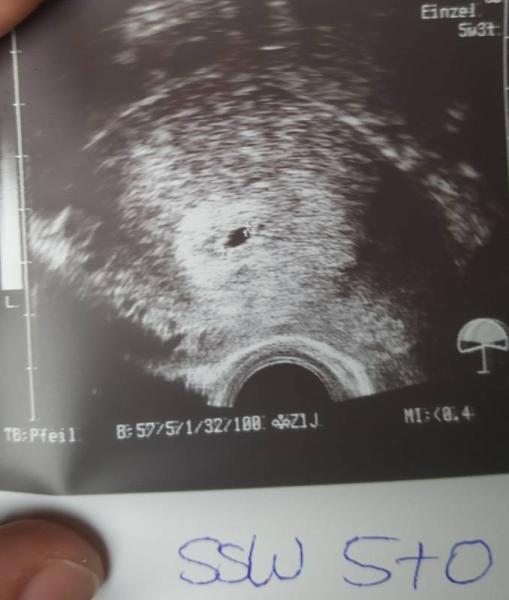

Hi Ich war heute ungeplant in der Kinderwunschklinik.(Blasenentzündung) Mir wurde noch mal Blut abgenommen und US gemacht. Bin heute 5+0 darf in 1 woche nochmal hin. Hat wer noch ein US aus so ner frühen Woche? Lg

Bild zu Termin in der KIWU - Forum für März - Mamis